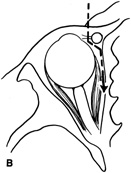

Although intraconal lesions medial to the nerve sometimes can be approached laterally, great care to identify and protect the optic nerve is required during deep orbital dissection. Because the eyelid crease incision allows such wide exposure of the superolateral orbit, it is often possible to remove fairly large orbital lesions without removing the lateral orbital wall (Fig. 9). Surgery in this case proceeds as described to exposure of the superior and lateral bony orbital rims. It is not necessary to reflect periosteum over the external surface of the rim. Instead, once periosteum at the rim is exposed, it is cut with cautery and then only the mesial periorbita need be elevated internally to expose orbital contents with subsequent intra-orbital dissection carried out with the lateral rim in place. Often it is preferable to initially attempt to remove intraconal or lacrimal fossa lesions in this fashion. If exposure proves inadequate, the periosteum over the external surface of the lateral orbital rim can be elevated and osteotomies and removal of the lateral wall still can be carried out.

Fig. 9. A,B. Coronal and axial CT images of a large intraconal neoplasm. C. Because it was felt to represent a well-encapsulated cavernous hemangioma, this lesion was a candidate for removal via an eyelid crease orbitotomy without bone removal. The eyelid crease incision marked. D. Incision made with scalpel. E. Orbicularis muscle is tented up and incised to expose the underlying septum. F. Dissection of a skin-muscle flap deep to orbicularis exposes the orbital septum and superior orbital bony rim. G. Cutting cautery is used to incise periosteum along the superior and lateral rims; finger palpation of the bone helps to direct this incision. H. Periorbita is elevated along the mesial surface of the lateral orbital rim in order to expose the deep orbital tissues. I. The cavernous hemangioma is visualized in the wound. Retraction is provided by one or more malleable retractors. J. Cryoprobe is affixed to the hemangioma to facilitate manipulation of the lesion. K. Large cavernous hemangioma after removal through the eyelid crease incision which was accomplished without bone removal. L. Periorbita is reattached over the lateral rim. M. The eyelid crease incision is closed with a running suture.